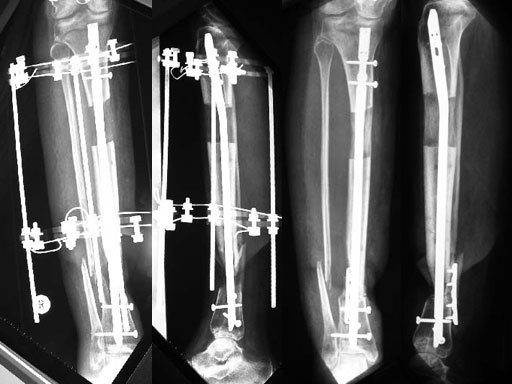

A 33-year-old female sustained a grade III open fracture of the right lower leg.

Case provided by Michael Raschke, Mnster, DE